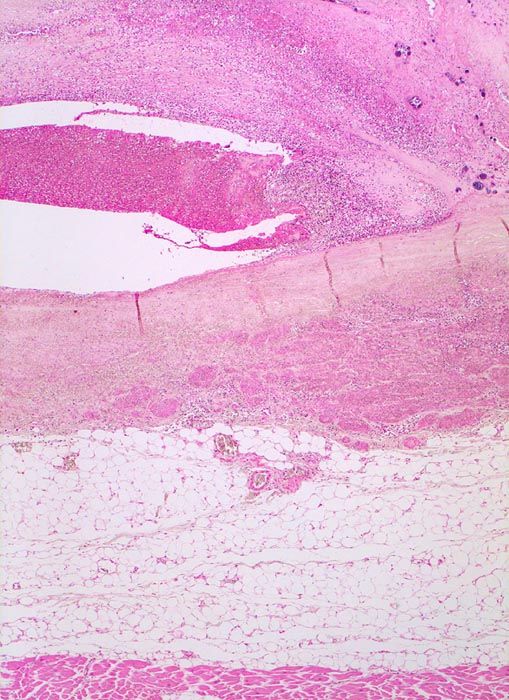

• Längsschnitt durch Aorta, Aortenklappe und linkes Ventrikelmyokard.

• Oben im Bild die Aorta mit kleinem Fibroatherom.

• Abszedierende Entzündung der aortalen Adventitia ausgehend von septikopyämischen Streuherden.

• Ulzerierte Aortenklappe(ulcerosa).

• Dem ulzerierten Klappengerüst aufgelagerte polypöse Vegetation aus Fibrin und Granulozyten durchsetzt von blauen Kokkenbakterienkolonien (polyposa).

• Ausgedehnte frische Koagulationsnekrose (unsichtbare Zellkerne, Infiltrate neutrophiler Granulozyten) des linken Ventrikelmyokards unterhalb der Klappe.

• Mehrere septikopyämische Streuherde (blaue Bakterienhaufen in intramyokardialen Blutgefässen umgeben von Mikroabszessen).